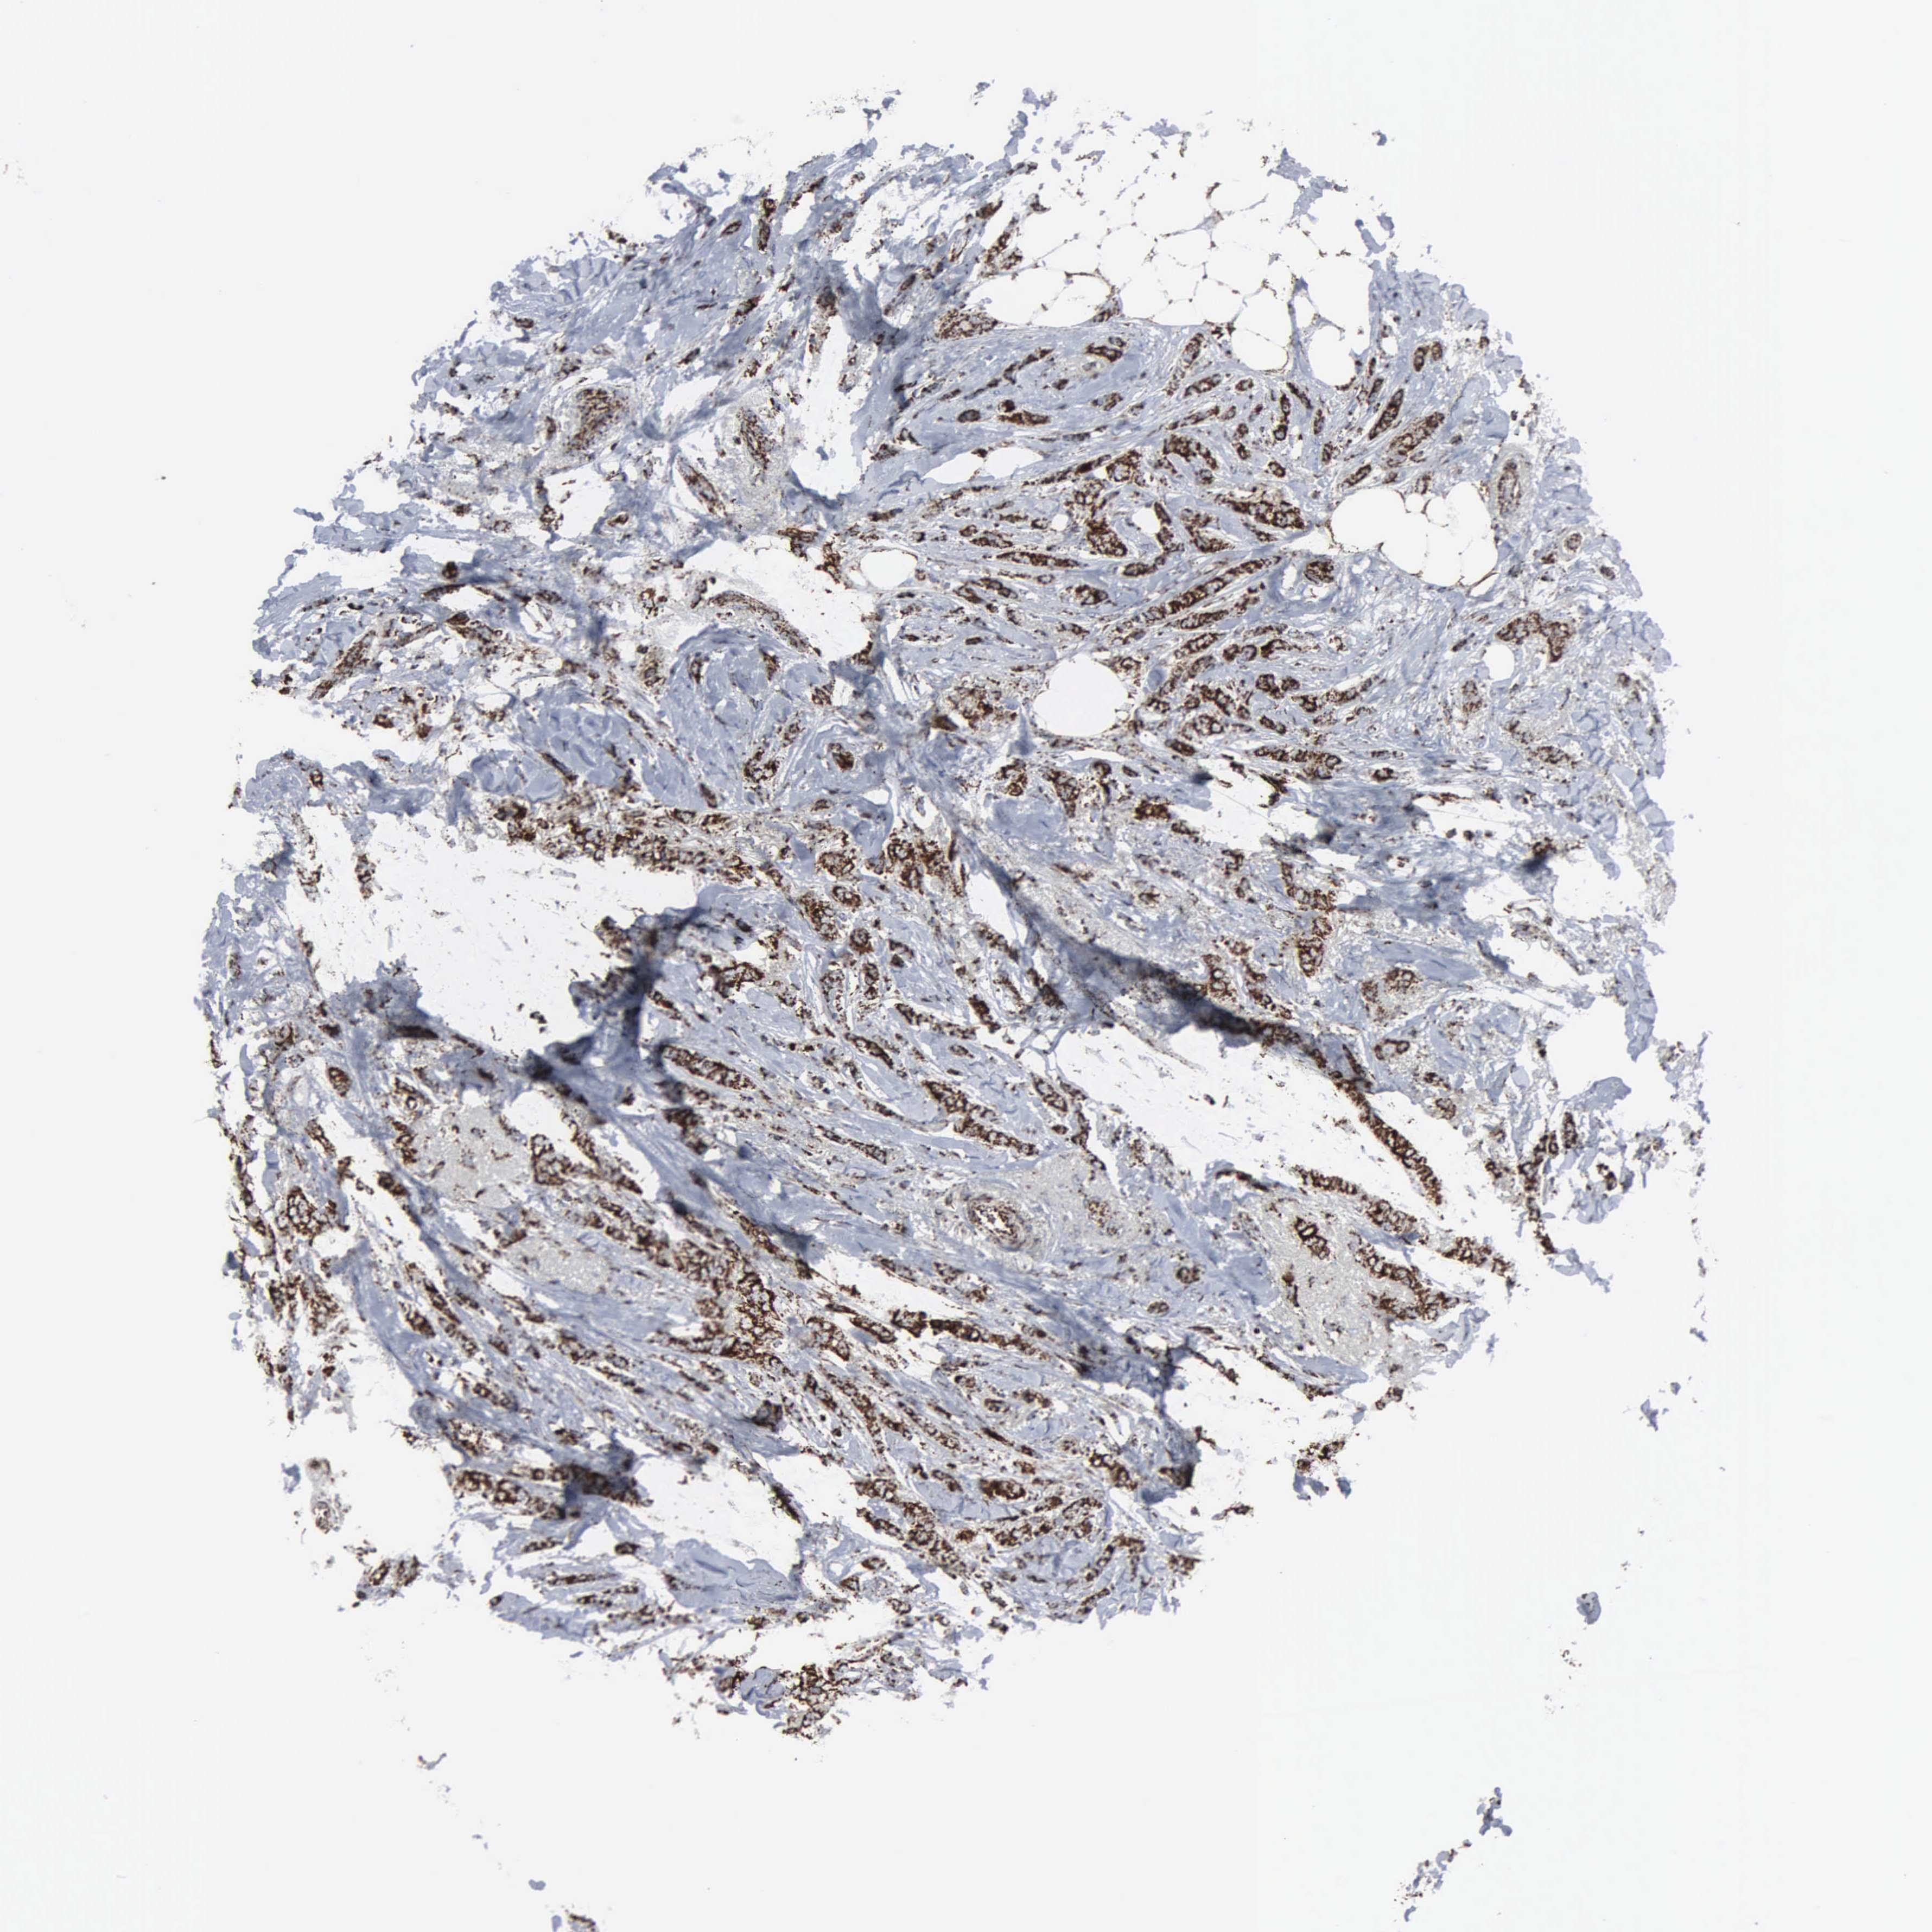

BRCA TCGA BRCA VALIDATION PROTEIN EXPRESSION

ANTIBODIES

AND

VALIDATION